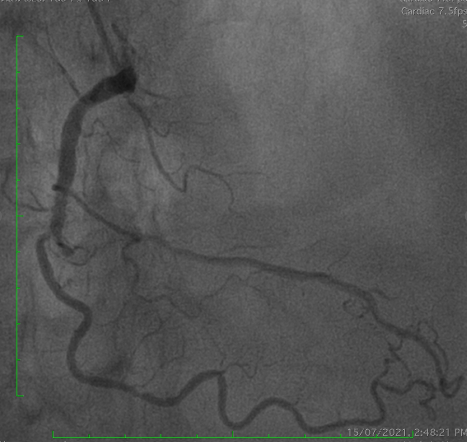

PCI was performed via single radial access with a 6F short-tip AL guiding catheter and Finecross microcatheter. 3D wiring with UB3 under orthogonal views; escalation to Gaia 3. Anchor ballooning in the RV branch improved support. The wire successfully crossed into the PLV. Predilation with a small balloon, followed by scoring ballooning. A Crusade dual-lumen catheter enabled Gaia 3 wiring into the PDA, which was predilated with a 2.5 mm balloon. IVUS revealed undersized and extensively malapposed stents contributing to ISR and prior very late thrombosis. High-pressure NC 3.75 mm ballooning improved expansion, though full correction was limited by the original stent size. A hybrid treatment strategy was chosen—DCB for both PLV and PDA (3.0¡¿20 mm and 3.0¡¿15 mm respectively, with DCB-assisted kissing), and DES reconstruction of the mid-to-proximal RCA using 4.0¡¿38 mm and 4.0¡¿20 mm stents delivered with guide extension support. Final IVUS confirmed optimal expansion and apposition without edge dissection. Final angiography showed TIMI 3 flow with no complications. At 9 months, angiography demonstrated patent RCA stents and positive remodeling at the PLV ostium.